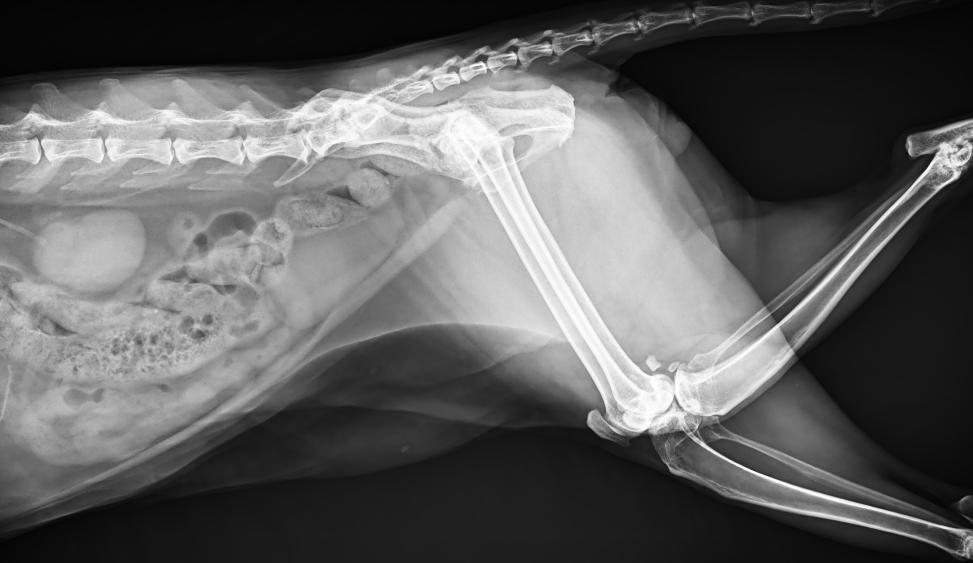

● 進口高品質球管,大功率、高熱容量、微焦點,1.0/2.0mm雙焦點設計

● 25kHz高主逆變頻率,輸出電壓更穩定;瞬時定格影像,無拖尾現象

● 智能高效的圖像處理軟件,大幅提升圖像質量